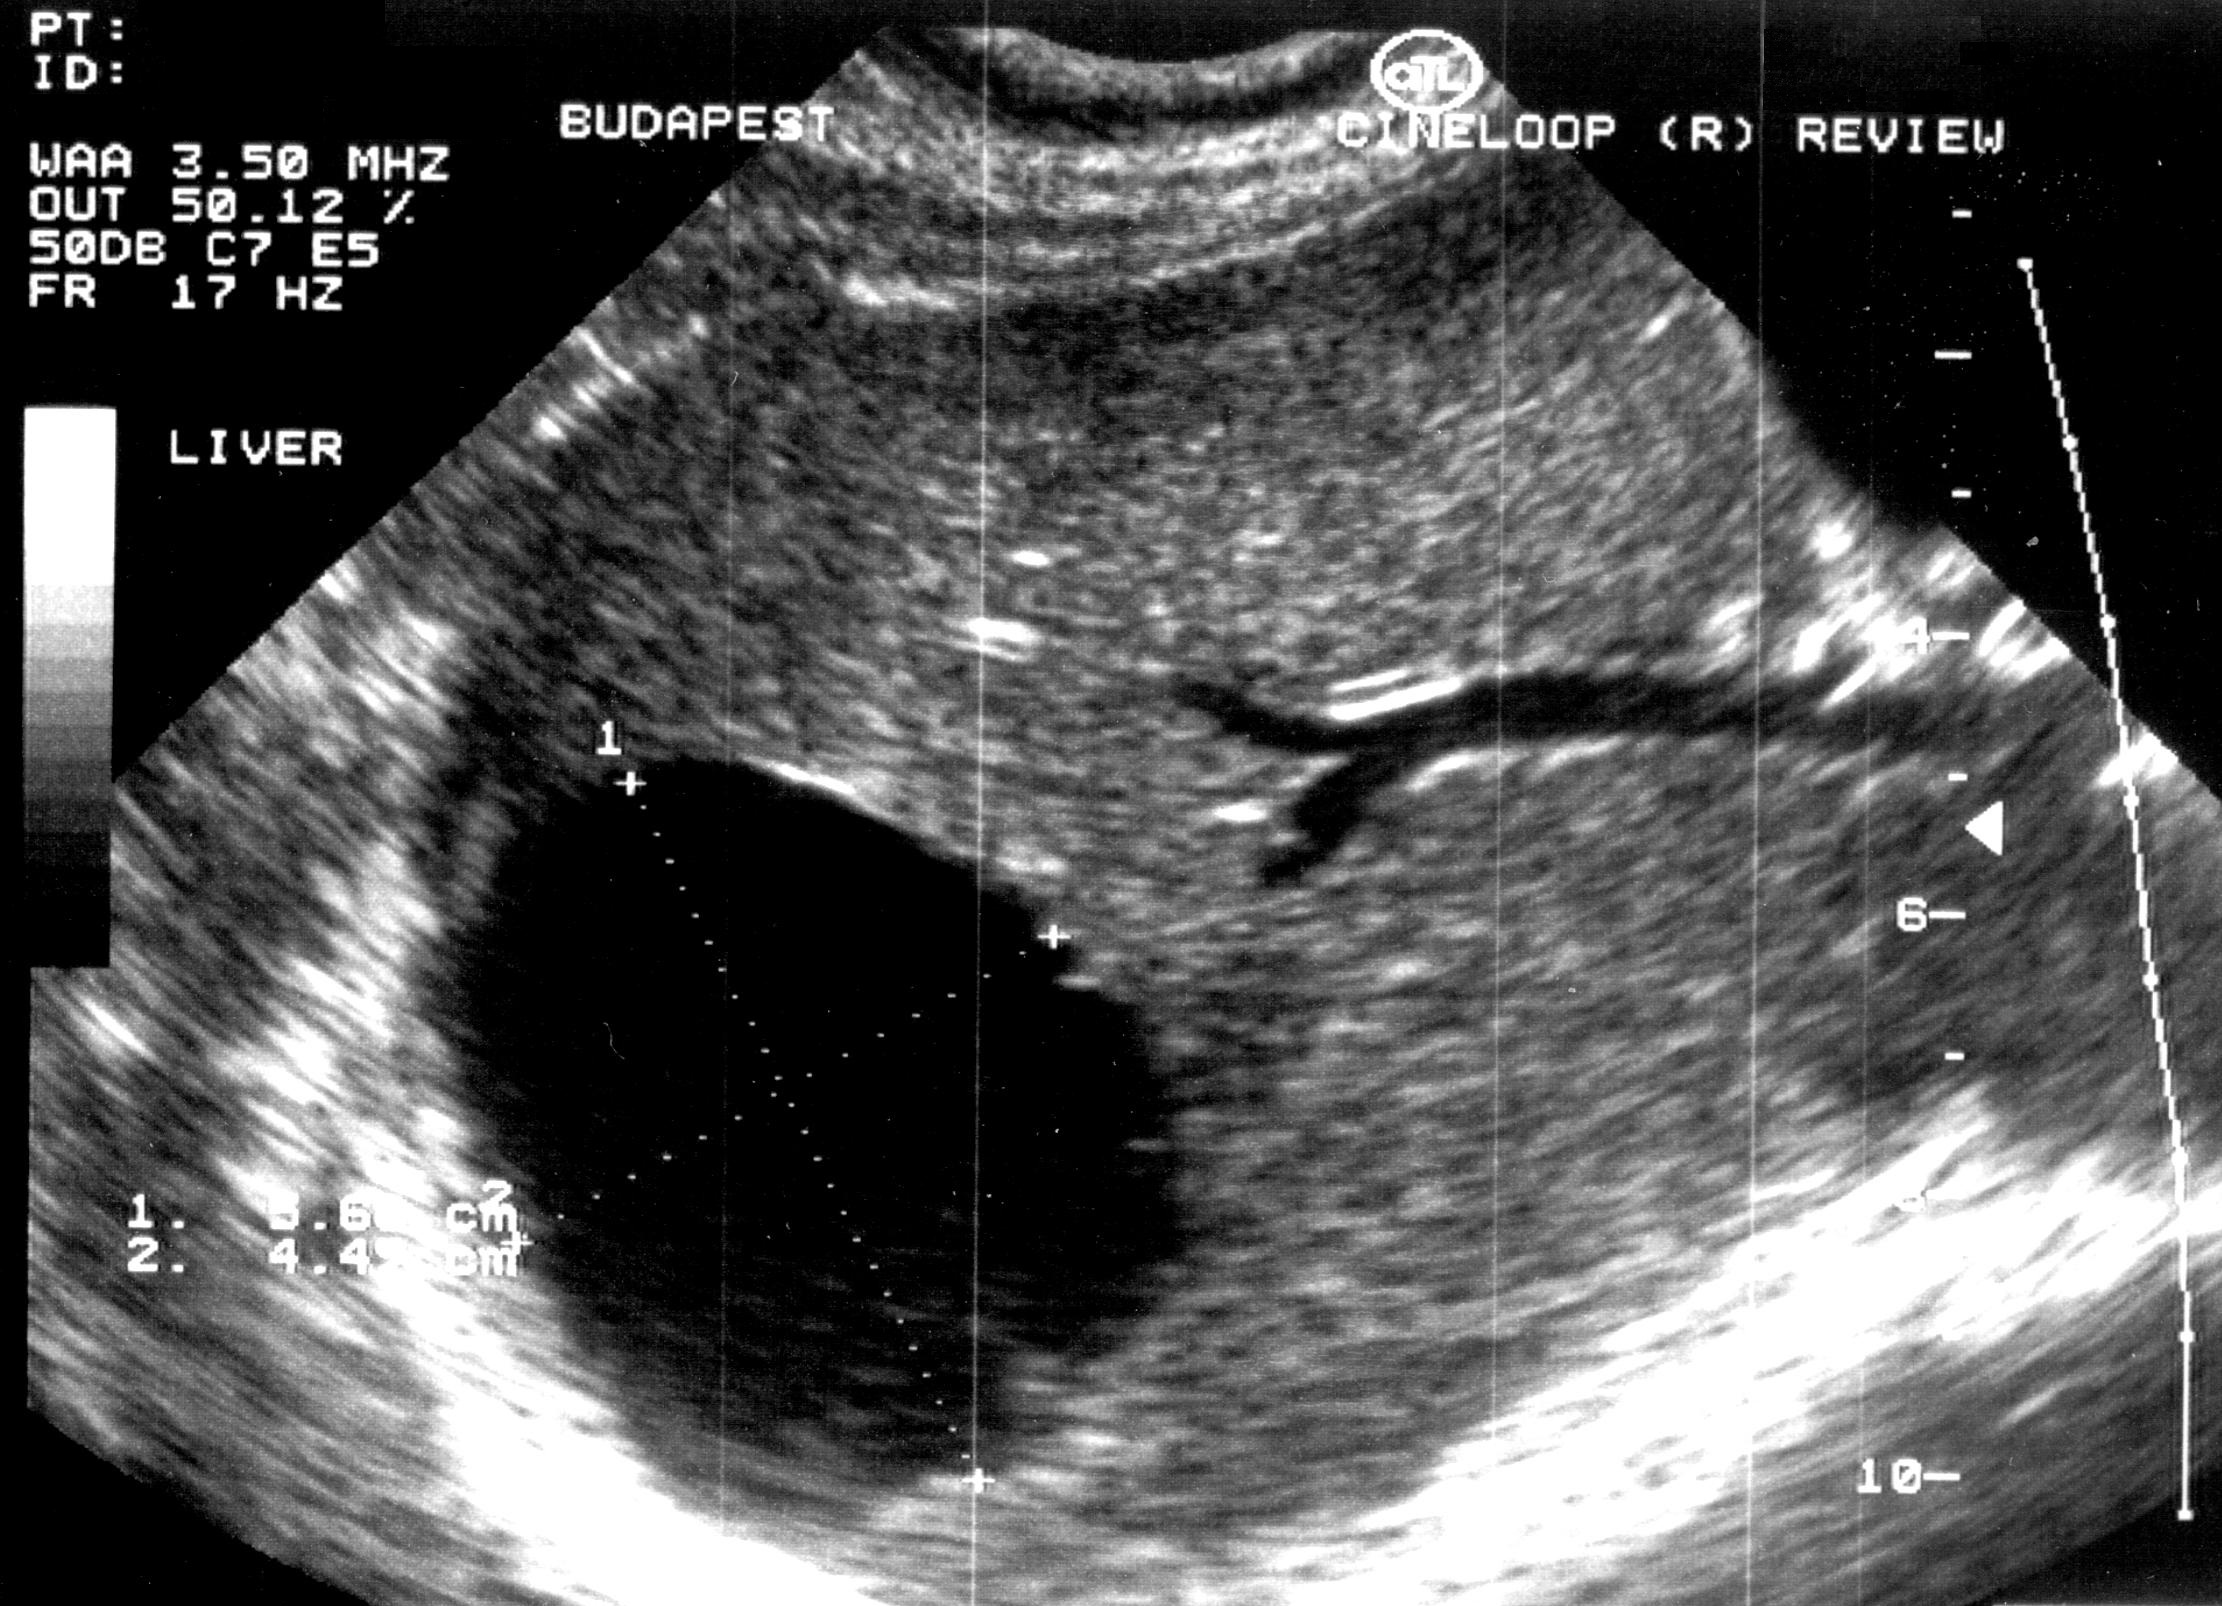

Compared to the surgical methods of past, nowadays these cystic lesions can be successfully treated percutaneously with alcoholic cyst sclerotization. (Figures 26., 27.).

Figure 27. – US and CT examinations before percutaneous ethanol sclerotization (A: US examination, B: CT examination)

The puncture of the cyst is usually guided with US (rarely with CT). The puncturing needs to take place from the parenchymal side of the cyst. When its contents are removed the empty cavity is filled up with diluted contrast material to ensure that there is no contrast leakage to the surroundings. The 96% ethanol is only injected after the contrast material has been removed and no leakage was found. (The volume of the alcohol should not exceed 50-60% of the cyst or 100 ml.)

The injected ethanol is left in the cyst for 20 minutes. Following this, the alcohol is drained as well. Cystic regression is then regularly controlled with US or CT examinations. (Figures 28., 29.) Patient complaints usually cease within 4-6 weeks after the treatment.